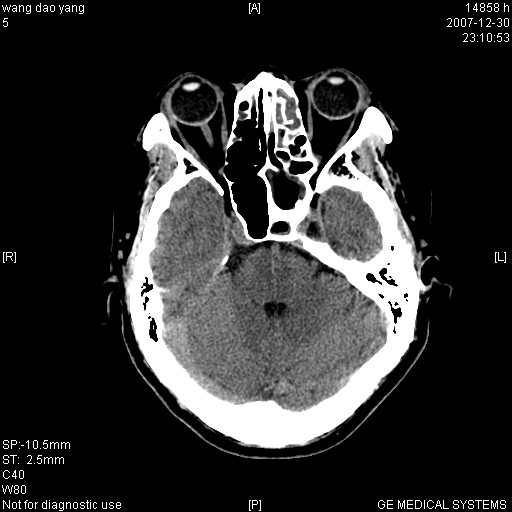

因外伤做ct

1。左侧筛窦蝶窦少量积液,2。右眼眶视神经鞘瘤可能性大,建议增强一下

外伤的话首先考虑球后血肿!!

右枕部有没有硬膜下血肿?

1筛窦血肿2球后血肿

病灶形态不规则,临床有外伤史,支持考虑:球后血肿!!!

球后肌锥内小团块状软组织密度影(性质待定);建议:行ct增强扫描或mri检查。

考虑血肿可能性大